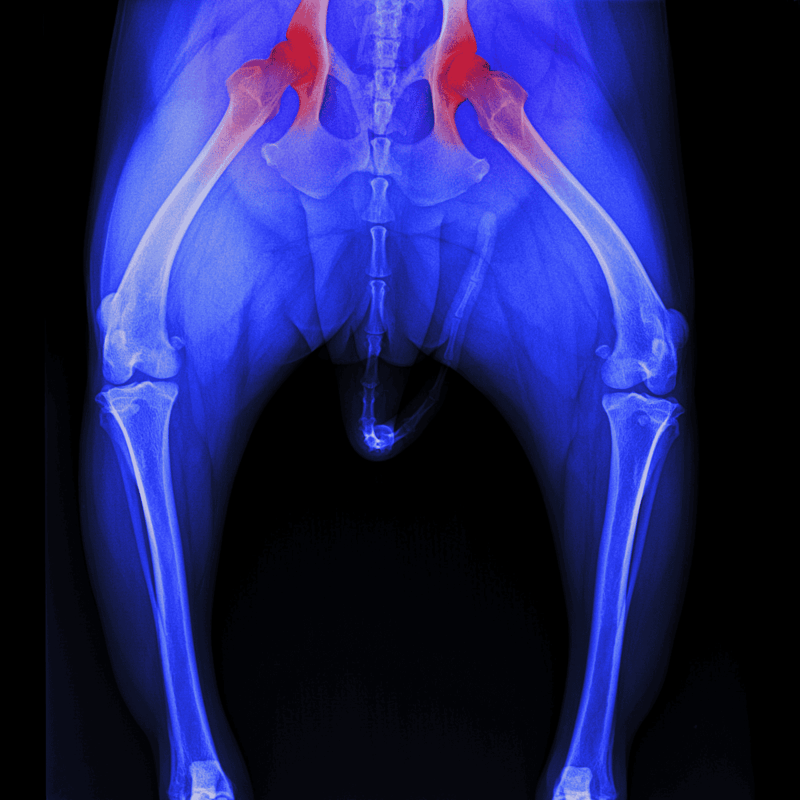

Chronic pain results from long-term conditions such as arthritis, cancer, or hip dysplasia. It is persistent and may worsen over time, causing significant stress to your dog and negatively impacting their quality of life.

Anti-inflammatory drugs can be prescribed for surgeries and long-term conditions like hip dysplasia, and osteoarthritis. These can also be used safely with medications like tramadol, gabapentin, or joint supplements.

| Glucosamine | Protects cartilage, used for hip dysplasia, spinal injuries | Tablets, chews, liquids | Over the counter |

| Chondroitin | Protects cartilage, used for hip dysplasia, spinal injuries | Tablets, chews, liquids | Over the counter |